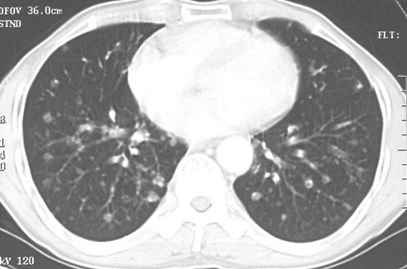

2020年临床执业医师实践技能第一站考点:肺转移癌的ct片成像

男性,55岁,结肠癌术后2年。(本题满分2.00分)

本题答案:D

题目解析:【该题针对“CT-肺癌”知识点进行考核】